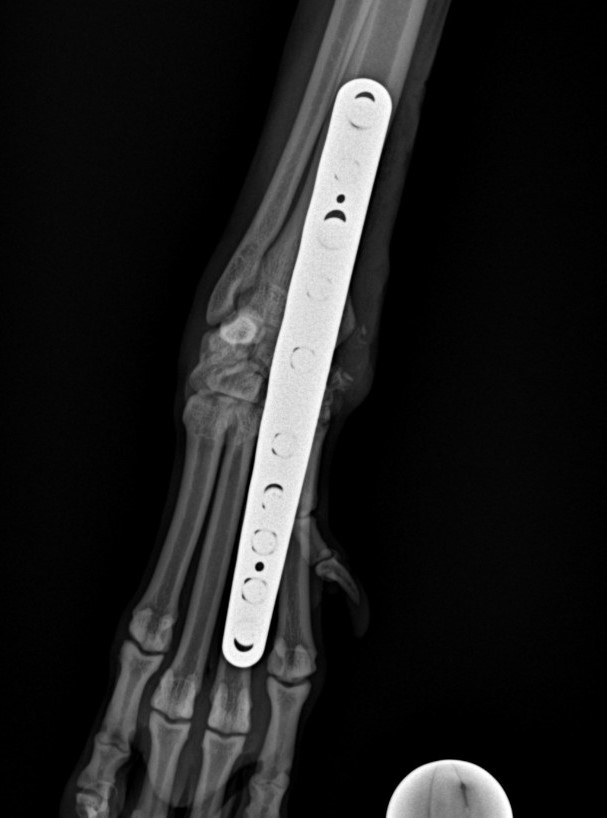

Artrodéza karpálního kloubu

Případy z praxe

Akutní

případ